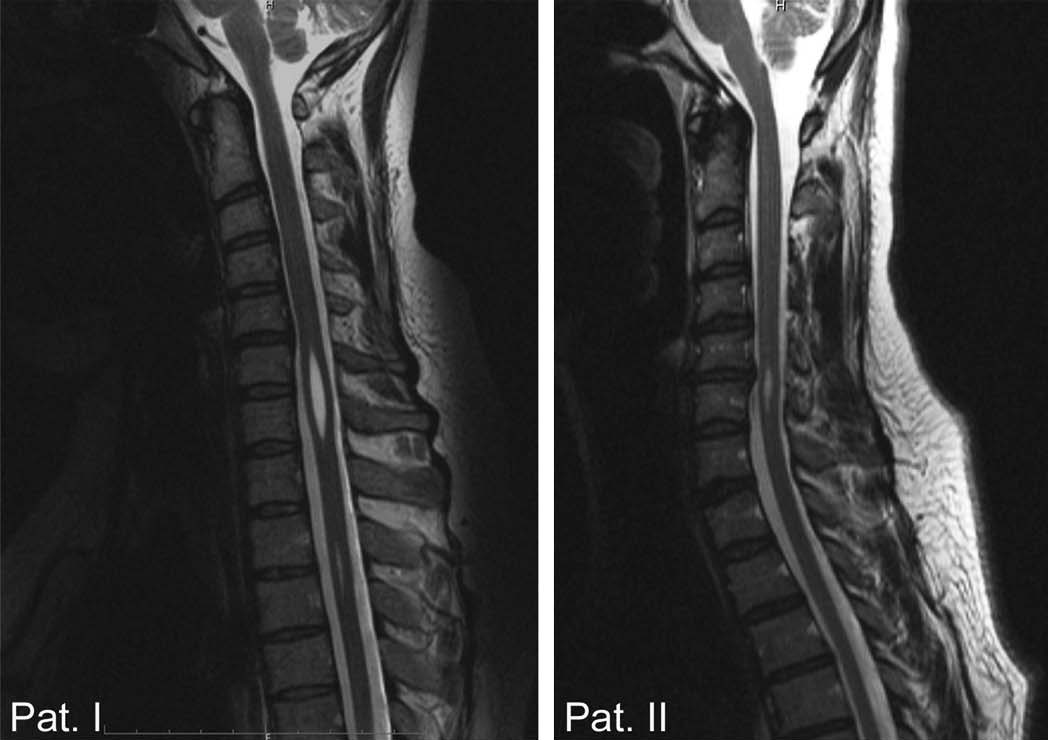

- МРТ – единственная методика, позволяющая максимально точно определить, насколько поврежден спинной мозг, выявить локализацию фиксации и другие нарушения.

«Золотым стандартом» диагностики позвоночника и спинного мозга является магнитно – резонансная томография (МРТ), позволяющая определить анатомо–морфологические взаимоотношения в сложной анатомической системе «спинной мозг — позвоночный канал — мягкие ткани, выявить скрытые формы спинальных пороков и уточнить прямые и косвенные признаки «фиксации спинного мозга». Патогномоничный симптом синдрома фиксированного спинного мозга — опущение конуса спинного мозга ниже L1 – L2 позвонка, с признаками утолщения конечной нити.

Новорожденным детям делают ультрасонографию. Взрослым назначают магнитно-резонансную томографию (МРТ), по результатам которой изучают строение спинномозгового канала. К компьютерной томографии (КТ) прибегают для осмотра костных структур позвоночника, например, перед хирургическим вмешательством.